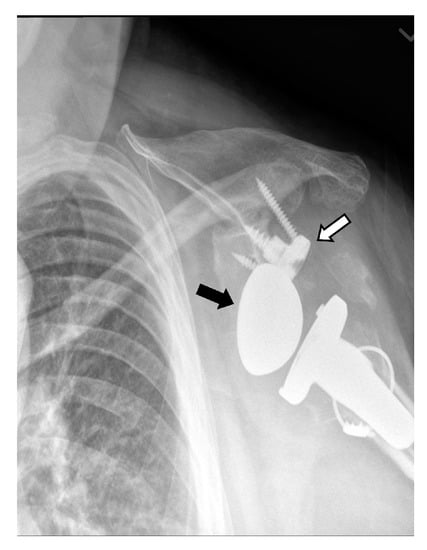

5.3. Revision Shoulder Arthroplasty